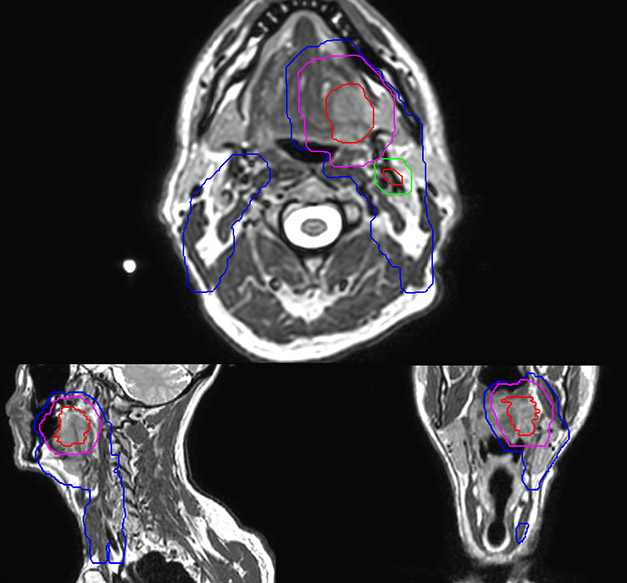

Epidermoid carcinoma of the left tongue base

The patient was diagnosed with an epidermoid carcinoma of the base of the left invading the amygdala lodge and the amygdaloglossal groove. Radiochemotherapy with curative aim was prescribed with a dose of 70 Gy for the tumor, 66 Gy on the suspicious nodes and 56 Gy on the elective drainage areas - in 33 fractions.

MR-based contouring and planning

MR based target contouring

MR-based target contouring on 3D T2W TSE in transversal, sagittal

and coronal planes.

Personalized VMAT dose

Personalized VMAT dose planned in Philips Pinnacle.